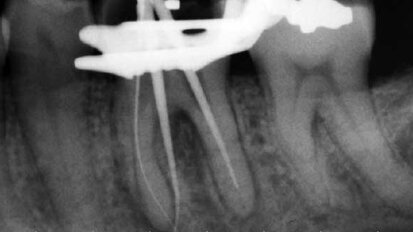

It’s never what you think it is

As a practicing endodontist over the past 25 five years, you believe you’ve seen whatever can walk in the door case wise. We are taught to look at ...